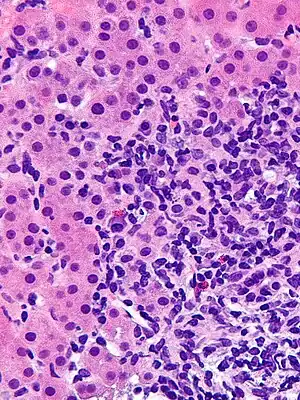

Giant cell transformation in autoimmune hepatitis -

Portal and periportal inflammatory infiltrate- interface hepatitis (piecemeal necrosis) arrow(s)